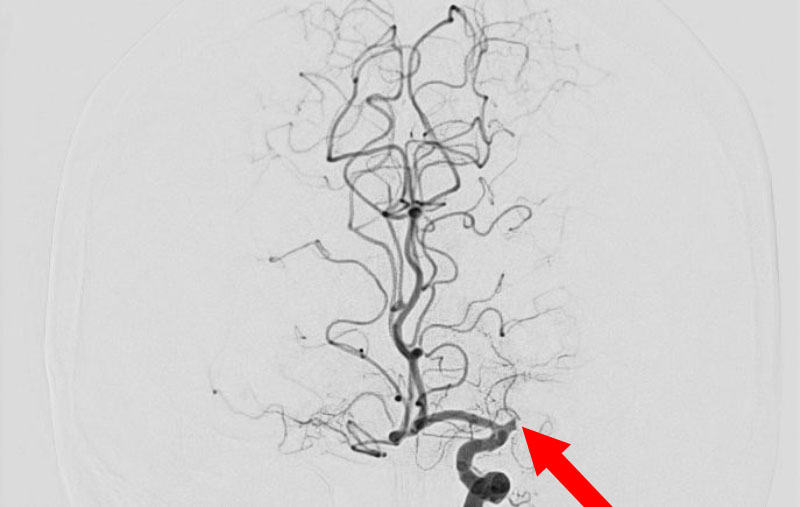

'25年11月

左内頚動脈脳動脈瘤

60代

大阪府の病院

No.1595 手術前